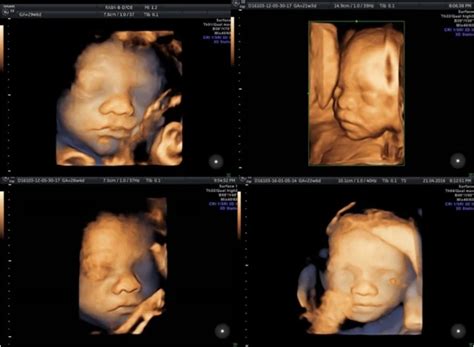

Pe parcursul sarcinii, este esențială monitorizarea atentă a dezvoltării fătului și a sănătății mamei. Ecografiile reprezintă principalul instrument de monitorizare, oferind imagini detaliate ale anatomiei și funcțiilor vitale. Prima ecografie, efectuată de obicei între săptămânile 6-8, confirmă viabilitatea sarcinii și detectează bătăile inimii. Ecografia morfologică din săptămânile 18-22 evaluează dezvoltarea organelor și poate identifica anomalii structurale.